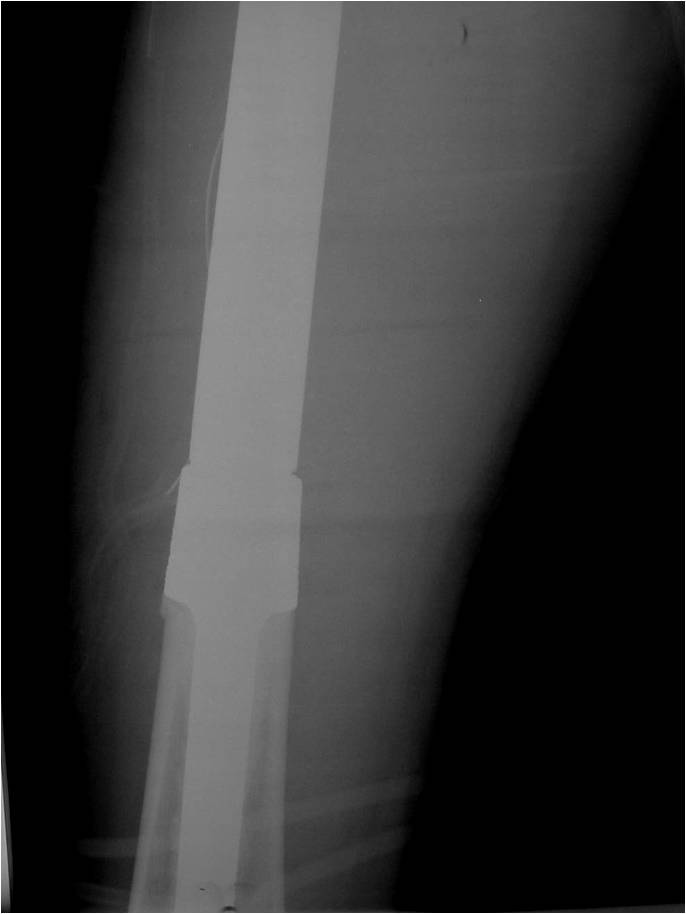

- Most protocols administer preoperative chemotherapy then surgery is performed. Surgery is followed by several courses of postoperative chemotherapy.

- Ewing sarcoma responds well to chemotherapy. Often there is a dramatic reduction in size of the tumor.

- Surgical resection

- Limb sparing surgery whenever feasible unless there will be a large leg length discrepancy that can not be accomodated for with surgery

If surgical resection is not feasible, radiation may be utilized for local control (instead of an amputation) since Ewing sarcoma is highly sensitive to radiation, at least as per the author’s opinion. There may be some tumors that are selectively treated with radiation instead of surgery however most patients as of 2008 are treated with limb sparing surgery whenever feasible. Sometimes radiation is used in conjunction with surgery if a wide margin was not obtained at the time of surgery. The decision to administer radiation depends on size of tumor, site of tumor, response of tumor to preoperative chemotherapy and risks vs benefits of radiation.